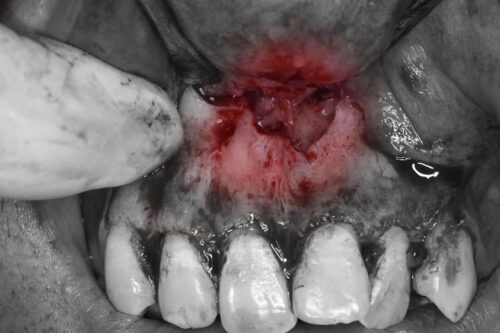

- Kích thích viêm nhiễm: Răng thừa ngầm có thể gây viêm nhiễm trong mô lợi hoặc mô xương xung quanh. Điều này có thể dẫn đến các triệu chứng như đau, sưng, và khó chịu.

- Tổn thương mô xương: Các răng thừa ngầm lâu ngày có thể tạo ra một lực không đều lên xương hàm, dẫn đến tổn thương hoặc tiêu xương.

Vì vậy, phẫu thuật lấy răng thừa ngầm là cần thiết để ngăn ngừa các biến chứng về sau, giúp bệnh nhân duy trì sức khỏe răng miệng và cải thiện thẩm mỹ khuôn mặt.